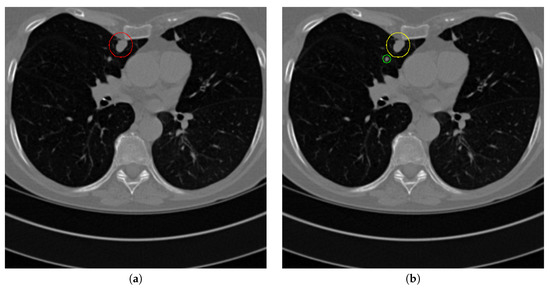

Figure 17 and Figure 18 illustrates the performance of pulmonary nodule detection by different methods on two example images in the LUNA16 dataset. In addition, Figure 19 and Figure 20 illustrates the performance of pulmonary nodule detection by different methods on two examples images in the TianChi dataset. As marked by green circles in Figure 18b,c and Figure 19c, the 3D-FCN and MR-CNN directly detected the nodule candidates from the original CT image without pre-processing, resulting in the incorrect determination of non-nodule tissue outside lung as nodule since the outside-lung organs are not filtered out from the nodule candidates. The 3D-UNET and PRN-HSN add the lung parenchyma region segmentation stage before detecting the nodule candidates inside-lung, so they provide better performance than 3D-FCN and MR-CNN in decreasing the over-estimation rate. However, they still suffer from unsatisfactory results for the following reasons: (1) the lung parenchyma segmentation is generated by simple thresholding with morphological operations so the near-edge regions are lost, shown as the one marked by yellow circle in Figure 20d,e; (2) the convolution kernel used in nodule candidate detection of 3D-UNET is with a small receptive field to learn global features from the image, so it is likely to confuse some small tissues as true nodules with small sizes, shown as the one marked by green circle in Figure 18d and Figure 20d; and (3) the proposed hierarchical saliency network (HSN) in PRN-HSN for nodule candidate classification omits the information with different resolutions, resulting in that the small-size nodule within the weakened, low-resolution region cannot be correctly recognized, as shown by the yellow circle in Figure 18e. The DCNN method simply applies the Faster RCNN method to provide good performance with low computational cost, but it may omit the nodules on the parenchymal edge shown as yellow circles in Figure 20f. CLAHE-SVM method adds a contrast-enhancement pre-processing before the nodule detection, leads to better performance on detecting nodules in the low-contrast region. However, it is easily to over-enhance the small-size tissues and over-estimate them as nodules, as shown by the green circles in Figure 19g andFigure 20g. The detection is also implemented over the whole image, so the nodule on the parenchyma edge may be under-estimated show by the yellow circle in Figure 20g. The Mask-RCNN method provides better effects than the above methods because of the good performance of Mask-RCNN in object detection. However, the performance is not stable for the small-size tissues and the irregular-shape nodule, shown by the green circles in Figure 17h and Figure 19h, and the yellow circle in Figure 19h. The proposed method takes the advantage of a series of U-Net-like networks to perform the nodule detection following a “coarse-to-fine” order of inside-lung region detection, nodule candidate detection and nodule determination. The U-Net network is modified by embedding inception structure, replacing the convolution and pooling by dilated convolution, and adapting multi-scale pooling and multi-resolution convolution connection, for different requirements of the three stages, respectively. Moreover, it makes use of the MSE loss, VGG-19-based perceptual loss as the complement of dice loss to optimize the whole framework. Therefore, as shown in Figure 17i, Figure 18i, Figure 19i and Figure 20i, the proposed framework provides superior performance on pulmonary nodule detection with low over-estimation of non-nodule tissues at the same time.

Figure 19. The result of detecting pulmonary nodules by different methods on one example image in TianChi dataset. Red circle represents the ground truth region of nodules, blue circles represent the correct estimation of pulmonary nodules, green circles represent the over-detected nodules, while yellow circles denote the nodules being omitted. (ai) are: ground truth nodule in the given chest CT image, nodule detected by 3D-FCN, MR-CNN, 3D-UNET, PRN-HSN, DCNN, CLAHE-SVM, MASK-RCNN and our proposed method.